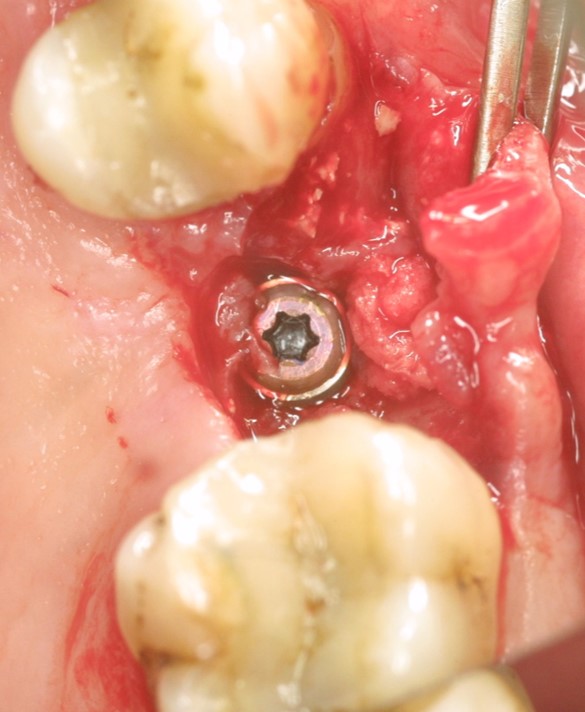

Implant insertion in atrophic alveolar ridge